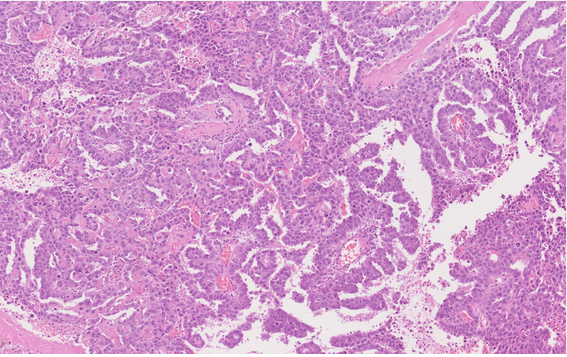

59M. Testicular mass

Dx?

Key features?

Dx: Spermatocytic tumour

Incidence peaksin the the sixth decade of life, with a mean age of 52–59 years. The tumours are rare in teenage boys and non-existent in children.

The most characteristic feature is a polymorphous cell population, often described as tripartite, consisting of three distinct cell types with distinguishing features based on cell size and chromatin: the small cells exhibit round, uniformly dense nuclei and scant cytoplasm; intermediate-sized cells have round nuclei with finely granular to filamentous (spireme) chromatin and variably prominent nucleoli; and giant cells have single or multiple nuclei with similar nuclear features to those of the intermediate-sized cells. Mitotic figures, including atypical forms, are usually frequent, as are a large number of apoptotic tumour cells. Unlike in a classic seminoma, prominent lymphocytic infiltrates are not present, and granulomatous inflammation is only rarely seen. Intratubular growth is common, but GCNIS is absent.

Essential: spermatocytic tumours typically occur in an older age group, with most patients in their fifth or sixth decade; tripartite microscopic appearance with three distinct cell types and without lymphocytic infiltrate or prominent fibrous septa; no immunoreactivity for usual embryonic germ cell tumour markers; no GCNIS.